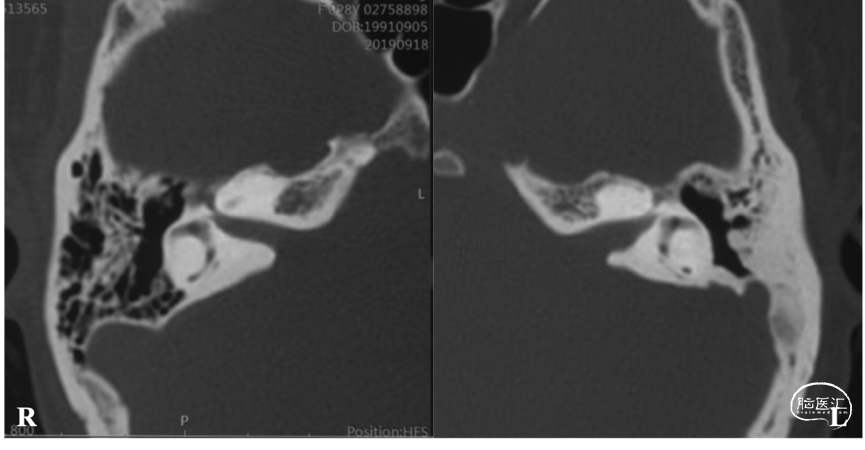

颅底CT骨窗位

CT骨窗位显示左侧内听道扩大,同时了解乙状窦、乳突导静脉位置及岩骨气化情况。